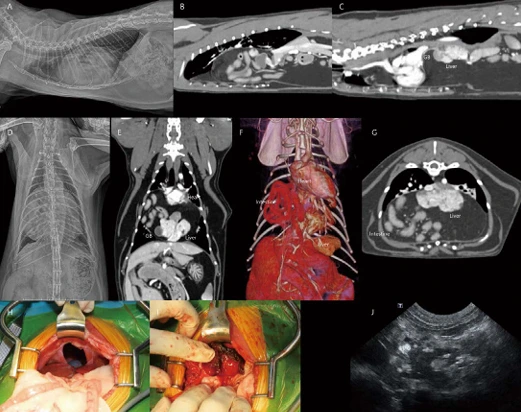

image.png?type=w966

8살 중성화 수컷 Scottish straight cat 5kg 환자가 노력성 호흡, 기력 저하로 내원하였습니다. 흉부방사선 검사에서 severe globoid cardiomegaly가 관찰됩니다. 외측상에서 심음영 전방으로 폐전엽으로 가는 폐혈관들이 얇게 관찰됩니다. Pulmonary hypoperfusion 상태로 고려됩니다. 소량의 흉수 및 patchy한 폐침윤 소견도 관찰됩니다(A, B). 심초음파에서는 다량의 심낭수가 관찰됩니다. 이로 인한 RA collapse, RV collapse, CVC plethora, 소량의 흉복수도 관찰됩니다(F, G). Cardiac tamponade 상태로 생각되어 매우 천천히 조심스럽게 심낭수 천자를 실시하였습니다(D). 심낭수는 transudate로 확인되었습니다. 심낭수 천자 후 환자는 일시적으로 호흡이 안정되었으며, 어느 정도 심낭수가 제거된 이후 심초음파에서 RA, RV collapse 소견은 개선되었습니다. Diffuse LV hypertrophy, severe LA dilation, smoke in the LA and Lau 등의 소견이 관찰되어, feline cardiomyopathy(hypertrophic phenotype)와 이로 인한 만성 다량의 심낭수, 소량의 흉수, 경등도의 심원성 폐부종, thromboembolism 상태로 임상적 가진단 하였습니다. 그러나 환자는 심낭수 천자 약 30분 이후부터 호흡 곤란이 심해졌고, 흉부방사선 검사에서 심한 acute pulmonary edema 진행되었습니다. 환자는 응급중환자실에서 적극적인 응급 처치를 시도하였지만, 객혈, 호흡 정지까지 빠르게 진행하였고, CPCR에 반응을 보이지 않고 사망하였습니다.

지난 시간 개의 심장/심낭막 질환 증례 보고에서도 있었던 Pericardial decompression syndrome (PDS) 발생 증례입니다. 이는 심낭천자술 후 발생할 수 있는 paradoxical 혈역학적 악화로 정의되며, 드물지만 치명적인 합병증입니다. 사람에서도 정확한 병태생리학은 알려져 있지 않지만, 혈역학, 허혈성, 자율신경계 불균형과 관련된 여러 메커니즘이 제시되어 있습니다(Yougeesh Prabhakar, Amandeep Goyal, Nauman Khalid, Nitish Sharma, Raj Nayyar, David H Spodick, and Lovely Chhabra. Pericardial decompression syndrome: A comprehensive review. World J Cardiol. 2019 Dec 26; 11(12): 282–291). 사람에서의 논문에 따르면, 심낭액을 제거한 후 정맥 환류 증가로 인한 우측 챔버 확장이 좌심실 충전 및 유효 심박출량에 영향을 줄 수 있고, 동시에, 전신 혈관 저항이 커짐에 따라 폐정맥 환류가 증가하면 부하 전후 불일치가 발생하여 울혈성 심부전이 발생할 수 있습니다. 추가 기여 요인으로는 심낭내압 증가가 최대 충혈 관상동맥 흐름에 영향을 미치는 것으로 알려져 있기 때문에 관상동맥 관류 장애로 인한 심근 허혈 및 기절이 있을 수 있습니다. 마지막으로, 삼출액 제거 후 교감신경 자극의 급격한 감소는 자율신경 불균형을 유발한다는 가설이 있습니다. 이러한 불균형은 순환 카테콜아민이 증가한 고아드레날린성 상태에서 명백하지 않았던 기존 심근 기능 장애가 압도적인 자율 신경 스트레스에 이차적으로 새로운 심근 기능 장애가 유도되기 때문에 발생하는 것으로 생각되고 있습니다. 이러한 PDS 위험 증가와 관련된 임상 요인에는 악성 질환, 방사선 치료 병력, 수축기 기능 저하를 동반한 기존 심근병증, 결합 조직 장애 등이 보고되어 있습니다. PDS의 발생 시기는 심낭 배액 후 환자의 혈역학이 일시적으로 초기 개선된 직후부터 며칠 이내로 다양하다고 보고되어 있습니다. 가장 일반적으로 폐부종을 동반한 급성 울혈성 심부전으로 나타납니다. 특별한 치료법도 예방법도 현재까지 입증된 바가 없으며, 다만 심초음파를 보면서 cardiac tamponade가 미약하게 완화될 정도까지만 심낭수를 매우 천천히 제거하는 것을 추천하고, 특히 종양 관련 삼출 또는 유의적 수준의 심실 dysfunction 환자에서 다량의 심낭수가 있을 경우 주의해야 합니다. 지난번 개의 증례는 종양 전이로 인한 다량의 심낭수 환자였고, 이번 고양이 증례는 심실 dysfunction이 있는 고양이 심근병증에서 다량의 심낭수 환자이므로, 심낭수 천자 시 위험 인자가 높은 상태였습니다. 그럼에도 불구하고 둘 다 심각한 cardiac tamponade였으므로, 심낭수 천자가 반드시 필요한 상태였습니다. PDS를 인지하고 매우 천천히 천자를 진행하였으나, 일시적 호흡 상태 회복 이후 짧은 시간 내로 사망하였습니다. 임상적으로 드물지만, 치명적일 수 있기 때문에 보호자 동의 및 충분한 설명이 필요합니다.